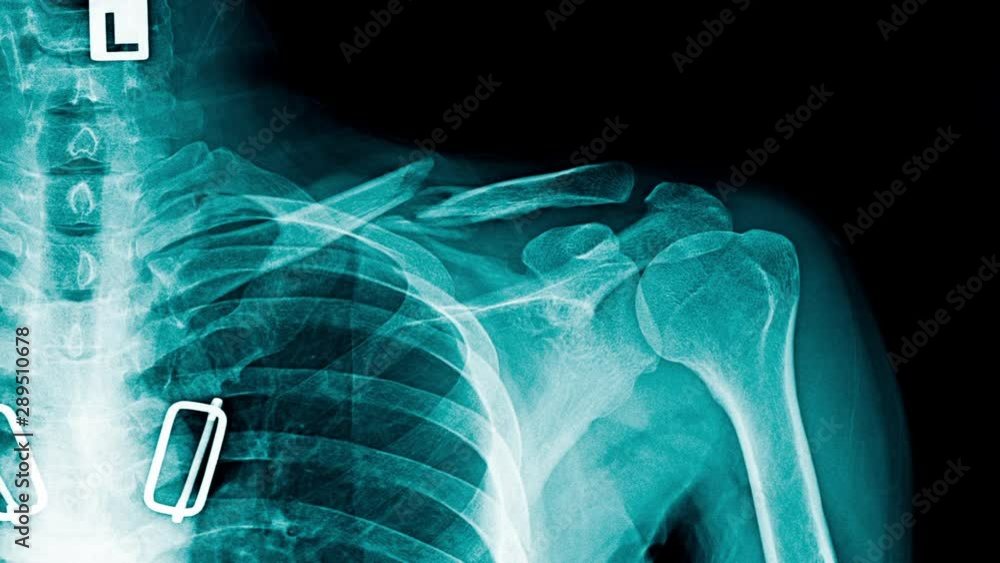

Xray Shoulder joint shoulder transaxillary view for diagnosis fracture Shoulder Pain X Ray Views Learn how to interpret scapula y view, one of the standard views for acute traumatic shoulder pain, and compare it with other views. Shoulder impingement describes a group of conditions characterized by the entrapment of musculoskeletal soft tissue within the shoulder, which primarily results in pain. Shoulder radiographs are often the only imaging exam necessary for the evaluation of acute. Shoulder Pain X Ray Views.

Anterior Shoulder Dislocation X Ray HopeanceHawkins Shoulder Pain X Ray Views Shoulder radiographs are often the only imaging exam necessary for the evaluation of acute shoulder trauma, calcific tendonitis,. For many patients with chronic shoulder pain, the typical recommended views are ap internal rotation, grashey or a second ap view with external rotation, and axillary views. Learn how to interpret scapula y view, one of the standard views for acute traumatic. Shoulder Pain X Ray Views.

Posterior Shoulder Dislocation • LITFL • Trauma Library Shoulder Pain X Ray Views Shoulder radiographs are often the only imaging exam necessary for the evaluation of acute shoulder trauma, calcific tendonitis,. For many patients with chronic shoulder pain, the typical recommended views are ap internal rotation, grashey or a second ap view with external rotation, and axillary views. Learn how to interpret scapula y view, one of the standard views for acute traumatic. Shoulder Pain X Ray Views.